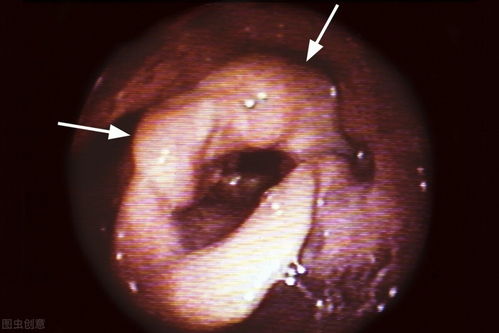

在皮肤的色素沉着中,我们常会遇到黑痣与黑色素瘤这两种看似相似却性质迥异的皮肤问题。黑痣,也称色素痣,是良性的皮肤肿瘤,而黑色素瘤则是一种恶性程度较高的皮肤癌。虽然黑痣有癌变的可能,但其概率相对较低,统计数据显示约为0.1%-1%。尽管如此,若黑痣出现以下变化,我们应保持警惕:

1. 生长不对称,形状不规则。边缘呈现锯齿状或其他不规则形状的改变。颜色混杂,从单一的色泽转变为多种颜色混杂。直径超过正常的5毫米范围。在较短时间内迅速增大或出现瘙痒、破溃等症状。这些都可能是黑痣恶变的信号。

尤其需要注意的是面部的黑痣,它们具有一些特殊性。面部黑痣十分常见,但需注意区分基底细胞癌与黑痣的区分,因为基底细胞癌有时会被误认为是普通的黑痣。面部长期受到紫外线的照射,因此需要定期观察黑痣的变化情况。面部摩擦部位(如鼻翼、耳后等)的黑痣风险略高,需要特别留意。